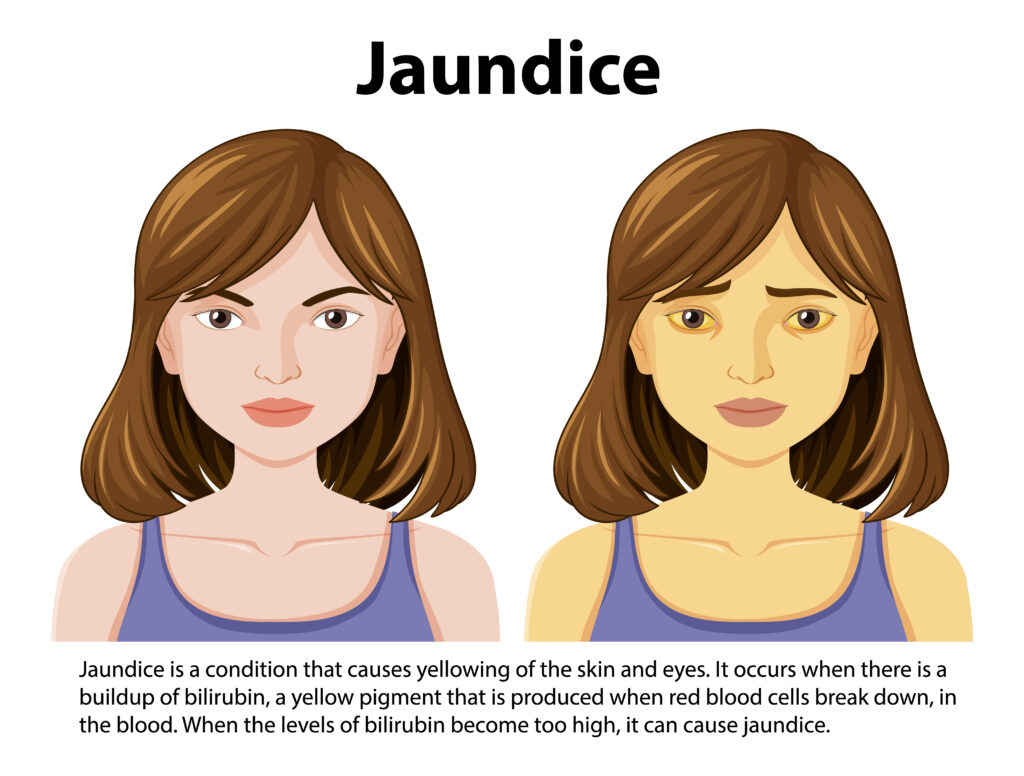

-Sarılık-

Sarılık, gözün içi ve derinin sarı renk almasıdır.

İdrarın rengi demli çay rengini andıracak şekilde koyulaşabilir. Kandaki bilirubin düzeyinin yükselmesi sarılığa neden olur.

Sarılığın Tedavisi ve Bakımı Nasıldır?

- Gözlerinizi ve derinizin rengini her gün bir ayna yardımı ile değerlendiriniz.

- Sarılık gelişirse zaman kaybetmeden sağlık kurumuna başvurunuz.

- Cildinizdeki renk değişikliğinden dolayı sosyal ilişkiler kurmaktan çekinmeyiniz.

- Aileniz ve arkadaşlarınızdan sizi rahatsız eden durumlar için destek isteyiniz.

Sağlık Kurumuna Ne Zaman Başvurulmalı?

ÖNEMLİ UYARI

-

Aşağıdaki belirtilerden biri varsa zaman kaybetmeden acil servise başvurunuz:

Gözlerinizin, derinizin rengi sarı renk alırsa

İdrarınızın rengi demli çay rengini andıracak şekilde koyulaşırsa